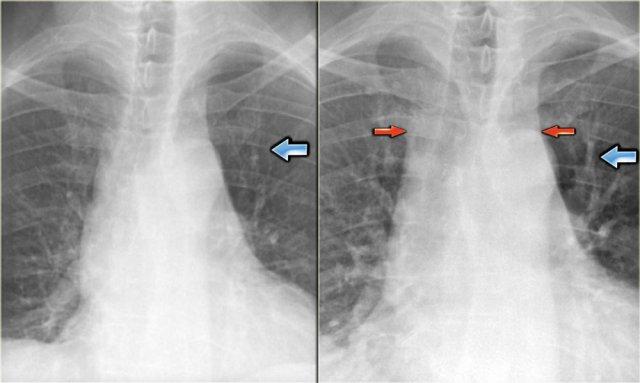

Hình ảnh các mạch máu thùy trên của bệnh nhân trong tình trạng bình thường (trái) và trong giai đoạn suy tim sung huyết (phải). Lưu ý độ rộng tăng lên của cuống mạch máu (mũi tên đỏ).

Giai đoạn I – Tái phân phối

Trên phim X-quang ngực bình thường với bệnh nhân đứng thẳng, các mạch máu phổi cấp máu cho vùng phổi trên có kích thước nhỏ hơn và số lượng ít hơn so với các mạch cấp máu cho nền phổi.

Giường mạch máu phổi có dự trữ dung lượng đáng kể; sự huy động có thể mở các mạch máu trước đó không được tưới máu và gây giãn các mạch đã được tưới máu.

Điều này dẫn đến hiện tượng tái phân phối lưu lượng máu phổi.

Đầu tiên là sự cân bằng lưu lượng máu, sau đó là tái phân phối dòng chảy từ các thùy dưới lên các thùy trên.

Thuật ngữ tái phân phối áp dụng cho các phim X-quang ngực chụp ở tư thế hít vào hoàn toàn và đứng thẳng.

Trong thực hành lâm sàng hàng ngày, nhiều phim X-quang ngực được chụp ở tư thế nằm ngửa hoặc nửa ngồi, và sự chênh lệch trọng lực giữa đỉnh phổi và nền phổi sẽ giảm đi.

Ở tư thế nằm ngửa, sẽ có sự cân bằng lưu lượng máu, có thể tạo ra ấn tượng giả về hiện tượng tái phân phối.

Trong những trường hợp này, việc so sánh với các phim cũ có thể hữu ích.

Tỷ lệ động mạch/phế quản

Bình thường, các mạch máu ở thùy trên nhỏ hơn phế quản đi kèm với tỷ lệ là 0,85 (3).

Ở mức rốn phổi, chúng có kích thước tương đương nhau, và ở thùy dưới, các động mạch lớn hơn với tỷ lệ là 1,35.

Khi có sự tái phân phối lưu lượng máu phổi, tỷ lệ động mạch/phế quản sẽ tăng lên ở các thùy trên và thùy giữa.

Điều này thể hiện rõ nhất ở vùng quanh rốn phổi.

Bên trái là hình ảnh bệnh nhân có tim to và tái phân phối.

Các mạch máu thùy trên có đường kính > 3 mm (bình thường 1-2 mm).

Lưu ý tỷ lệ động mạch/phế quản tăng ở mức rốn phổi (mũi tên).